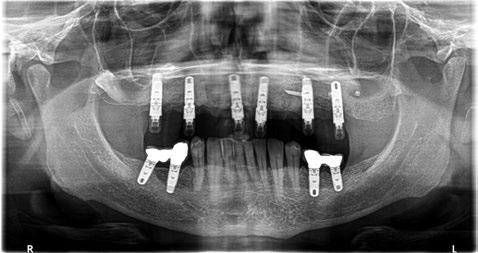

Figura 16. Ortopantomografía postoperatoria.

y lo que se pudo preservar del hueso malar. Se añadió una malla sinterizada infraorbitaria para dar volumen a la mejilla y se planificaron dos brazos de conexión que emergieran en las posiciones 24 y 26 de forma subgingival (Figuras 8 y 9). La superficie interna que apoyaba en el hueso era de titanio microrrugoso, y la superficie externa y conectores de titanio pulido y hexágono externo universal (Figuras 10 y 11). La cirugía se hizo bajo anestesia general en infiltración con anestesia local (4% articaína, 1:100.00 epinefrina), levantando el

colgajo cutáneo de la mejilla por vía intraoral, preservando el colgajo temporal para no comunicar con el remanente de la cavidad naso maxilar (Figura 12). Se emplearon 10 tornillos de osteosíntesis de 1,9 mm y la estabilidad primaria obtenida fue excelente (Figura 13)

Posición de los tornillos de osteosíntesis y emergencia de las conexiones.

Figura

Figura 9.